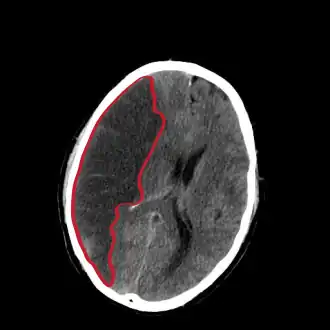

Corte de una TAC del cerebro mostrando un infarto cerebral del hemisferio derecho (lado izquierdo de la imagen). | ||

La tomografía de cráneo revela zonas de infarto mayores de 1,6 cm, pero los cambios de la densidad no son inmediatos, por lo que es un estudio poco sensible. Además de la TC sin contraste, la inyección de contraste permite realizar una TC de perfusión y una angio-TC (angiotomografía). El 80 % de las enfermedades cerebrovasculares son debidas a un infarto cerebral isquémico y el otro 20 % a una hemorragia cerebral.[2] Un infarto debe distinguirse de una hemorragia cerebral y de una hemorragia subaracnoidea. Los infartos cerebrales varían en cuanto a gravedad, pues en un tercio de ellos se acaba produciendo la muerte del individuo.